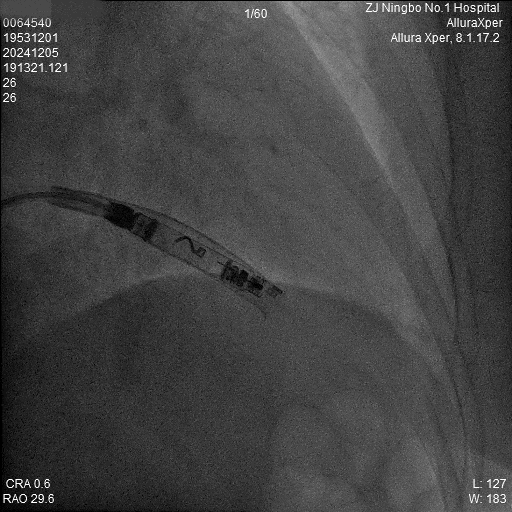

6.释放:释放Aveir VR后,最终影像图。

b) RAO 30

c) LAO 40